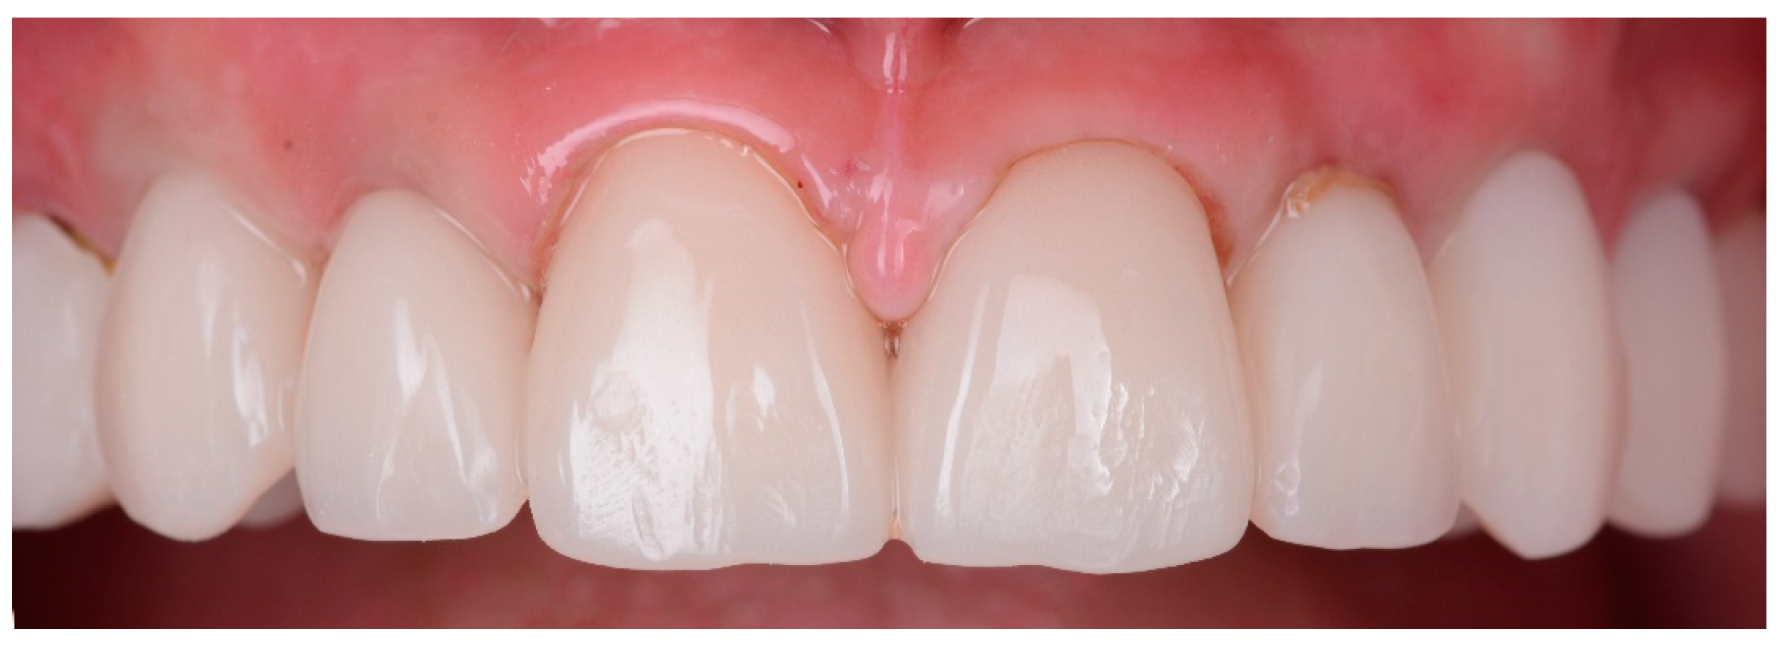

- Final restorations placement